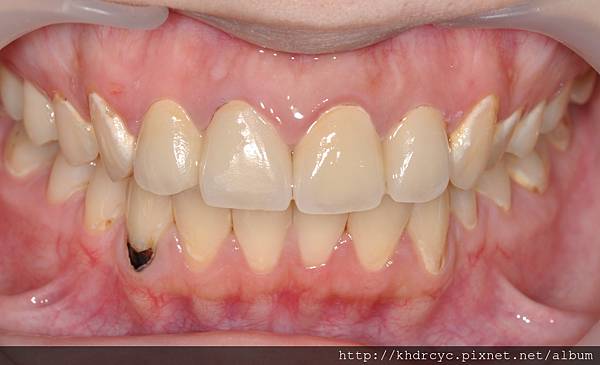

欣美牙醫首先幫仁武的C小姐

完成門牙治療包括根管治療與牙周病

改善牙齒結構與牙肉健康

配合療程仁武的C小姐裝上全瓷假牙套

美觀立刻得到改善

已經忍受門牙爛掉的問題很久